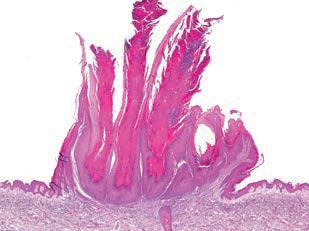

Obr. 1 Verruca vulgaris.Bradavice je epitelová hyperplazie imponující nezávisle na lokalizaci jako malá plochá papula s drsným povrchem až květákovitý šedožlutý nodulus (obr. 1, 2). Typické jsou bodovité kapilární trombózy viditelné často jako červené až černé body. Diagnóza je možná většinou již pohledem.

Obr. 2 Histopatologický obraz verruca vulgaris.Klasická bradavice se vyskytuje i v oblasti dutiny ústní, nejčastěji v oblastech sliznic spojovaných s ortokeratotickým procesem – rty, gingiva, tvrdé patro.